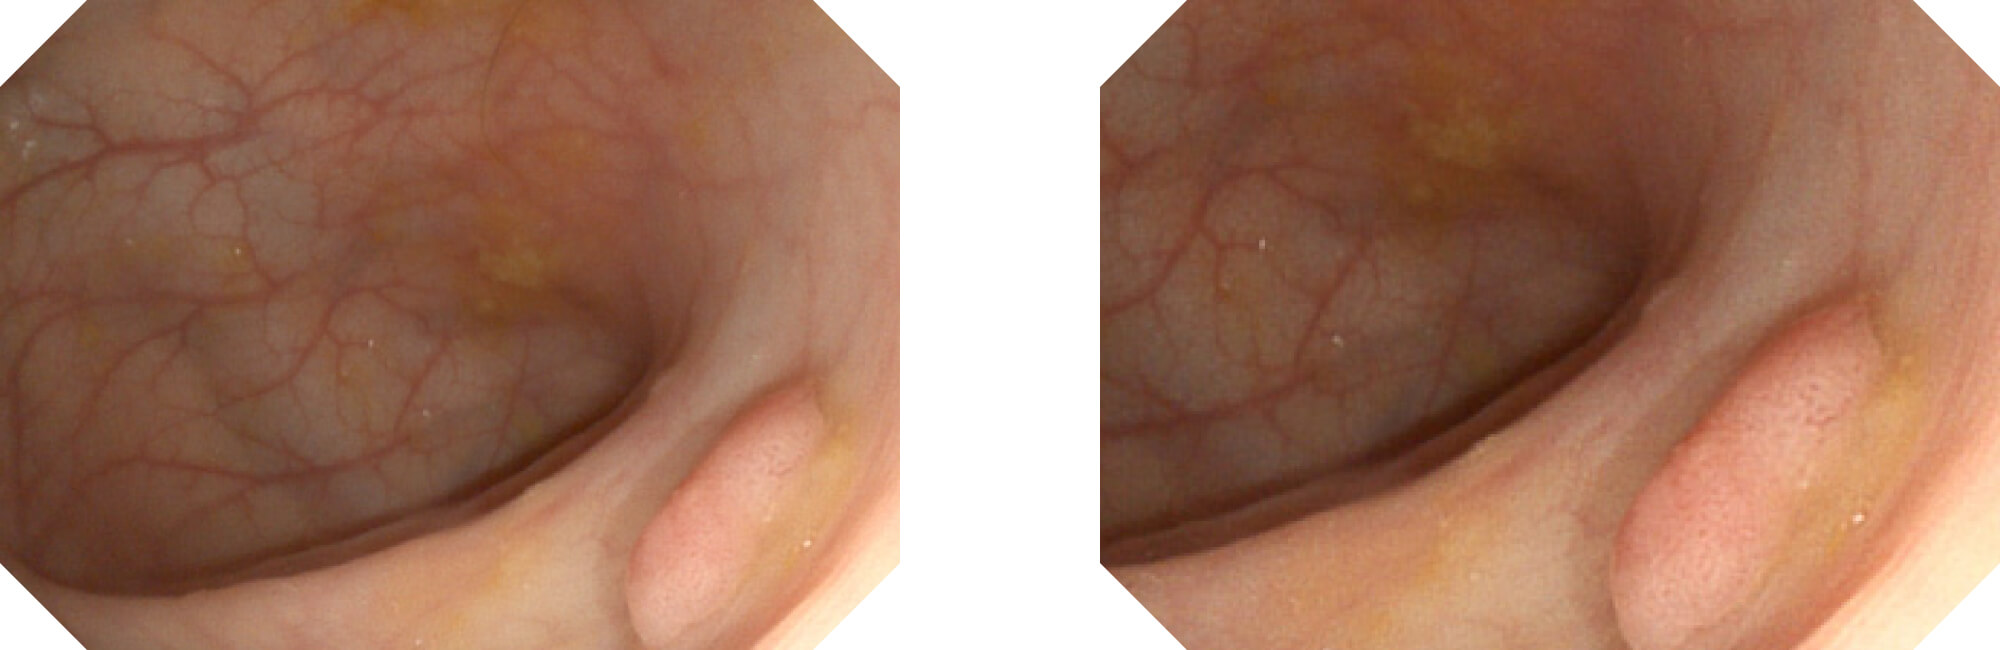

高清数字信号结合构造强调和色彩增强,多重图像处理技术能让每一个图像都清晰可见。

构造强调

色彩增强

电子放大